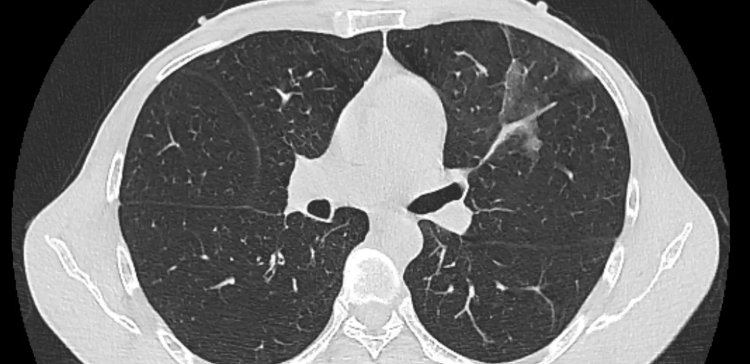

CT는 ‘Computed Tomography’의 약자로, 인체의 단면을 수백 장 이상 촬영한 뒤 컴퓨터가 이를 합성하여 입체적인 이미지를 만들어냅니다. 엑스레이는 한 방향에서 찍은 단일 평면 이미지이기 때문에, 가슴 속 구조가 겹쳐 보이는 한계가 있습니다. 반면 CT는 다양한 각도에서 찍은 단층 이미지를 결합하므로, 기관이나 폐 속 병변의 위치와 크기를 훨씬 정확히 확인할 수 있습니다.

예를 들어 엑스레이에서는 갈비뼈 그림자에 가려진 작은 결절이 보이지 않더라도, CT에서는 뚜렷하게 구분됩니다. 이처럼 세밀한 관찰이 가능하기 때문에, 흉부ct로 볼수있는 질환은 폐렴이나 결핵 같은 감염성 질환을 넘어 종양, 혈관 이상, 심장 주위 구조의 이상까지 포함됩니다.

흉부CT가 가장 자주 사용되는 영역은 폐입니다. 폐암, 폐결절, 폐렴, 결핵, 기관지 확장증, 폐기종, 폐섬유화증 등 다양한 질환을 세밀히 구분할 수 있습니다. 특히 폐암의 경우 초기에는 증상이 거의 없기 때문에, CT를 통한 조기 발견이 매우 중요합니다. 또한 흡연자의 폐 손상 정도를 평가하거나, 미세한 염증이 반복되는 패턴도 파악할 수 있습니다.